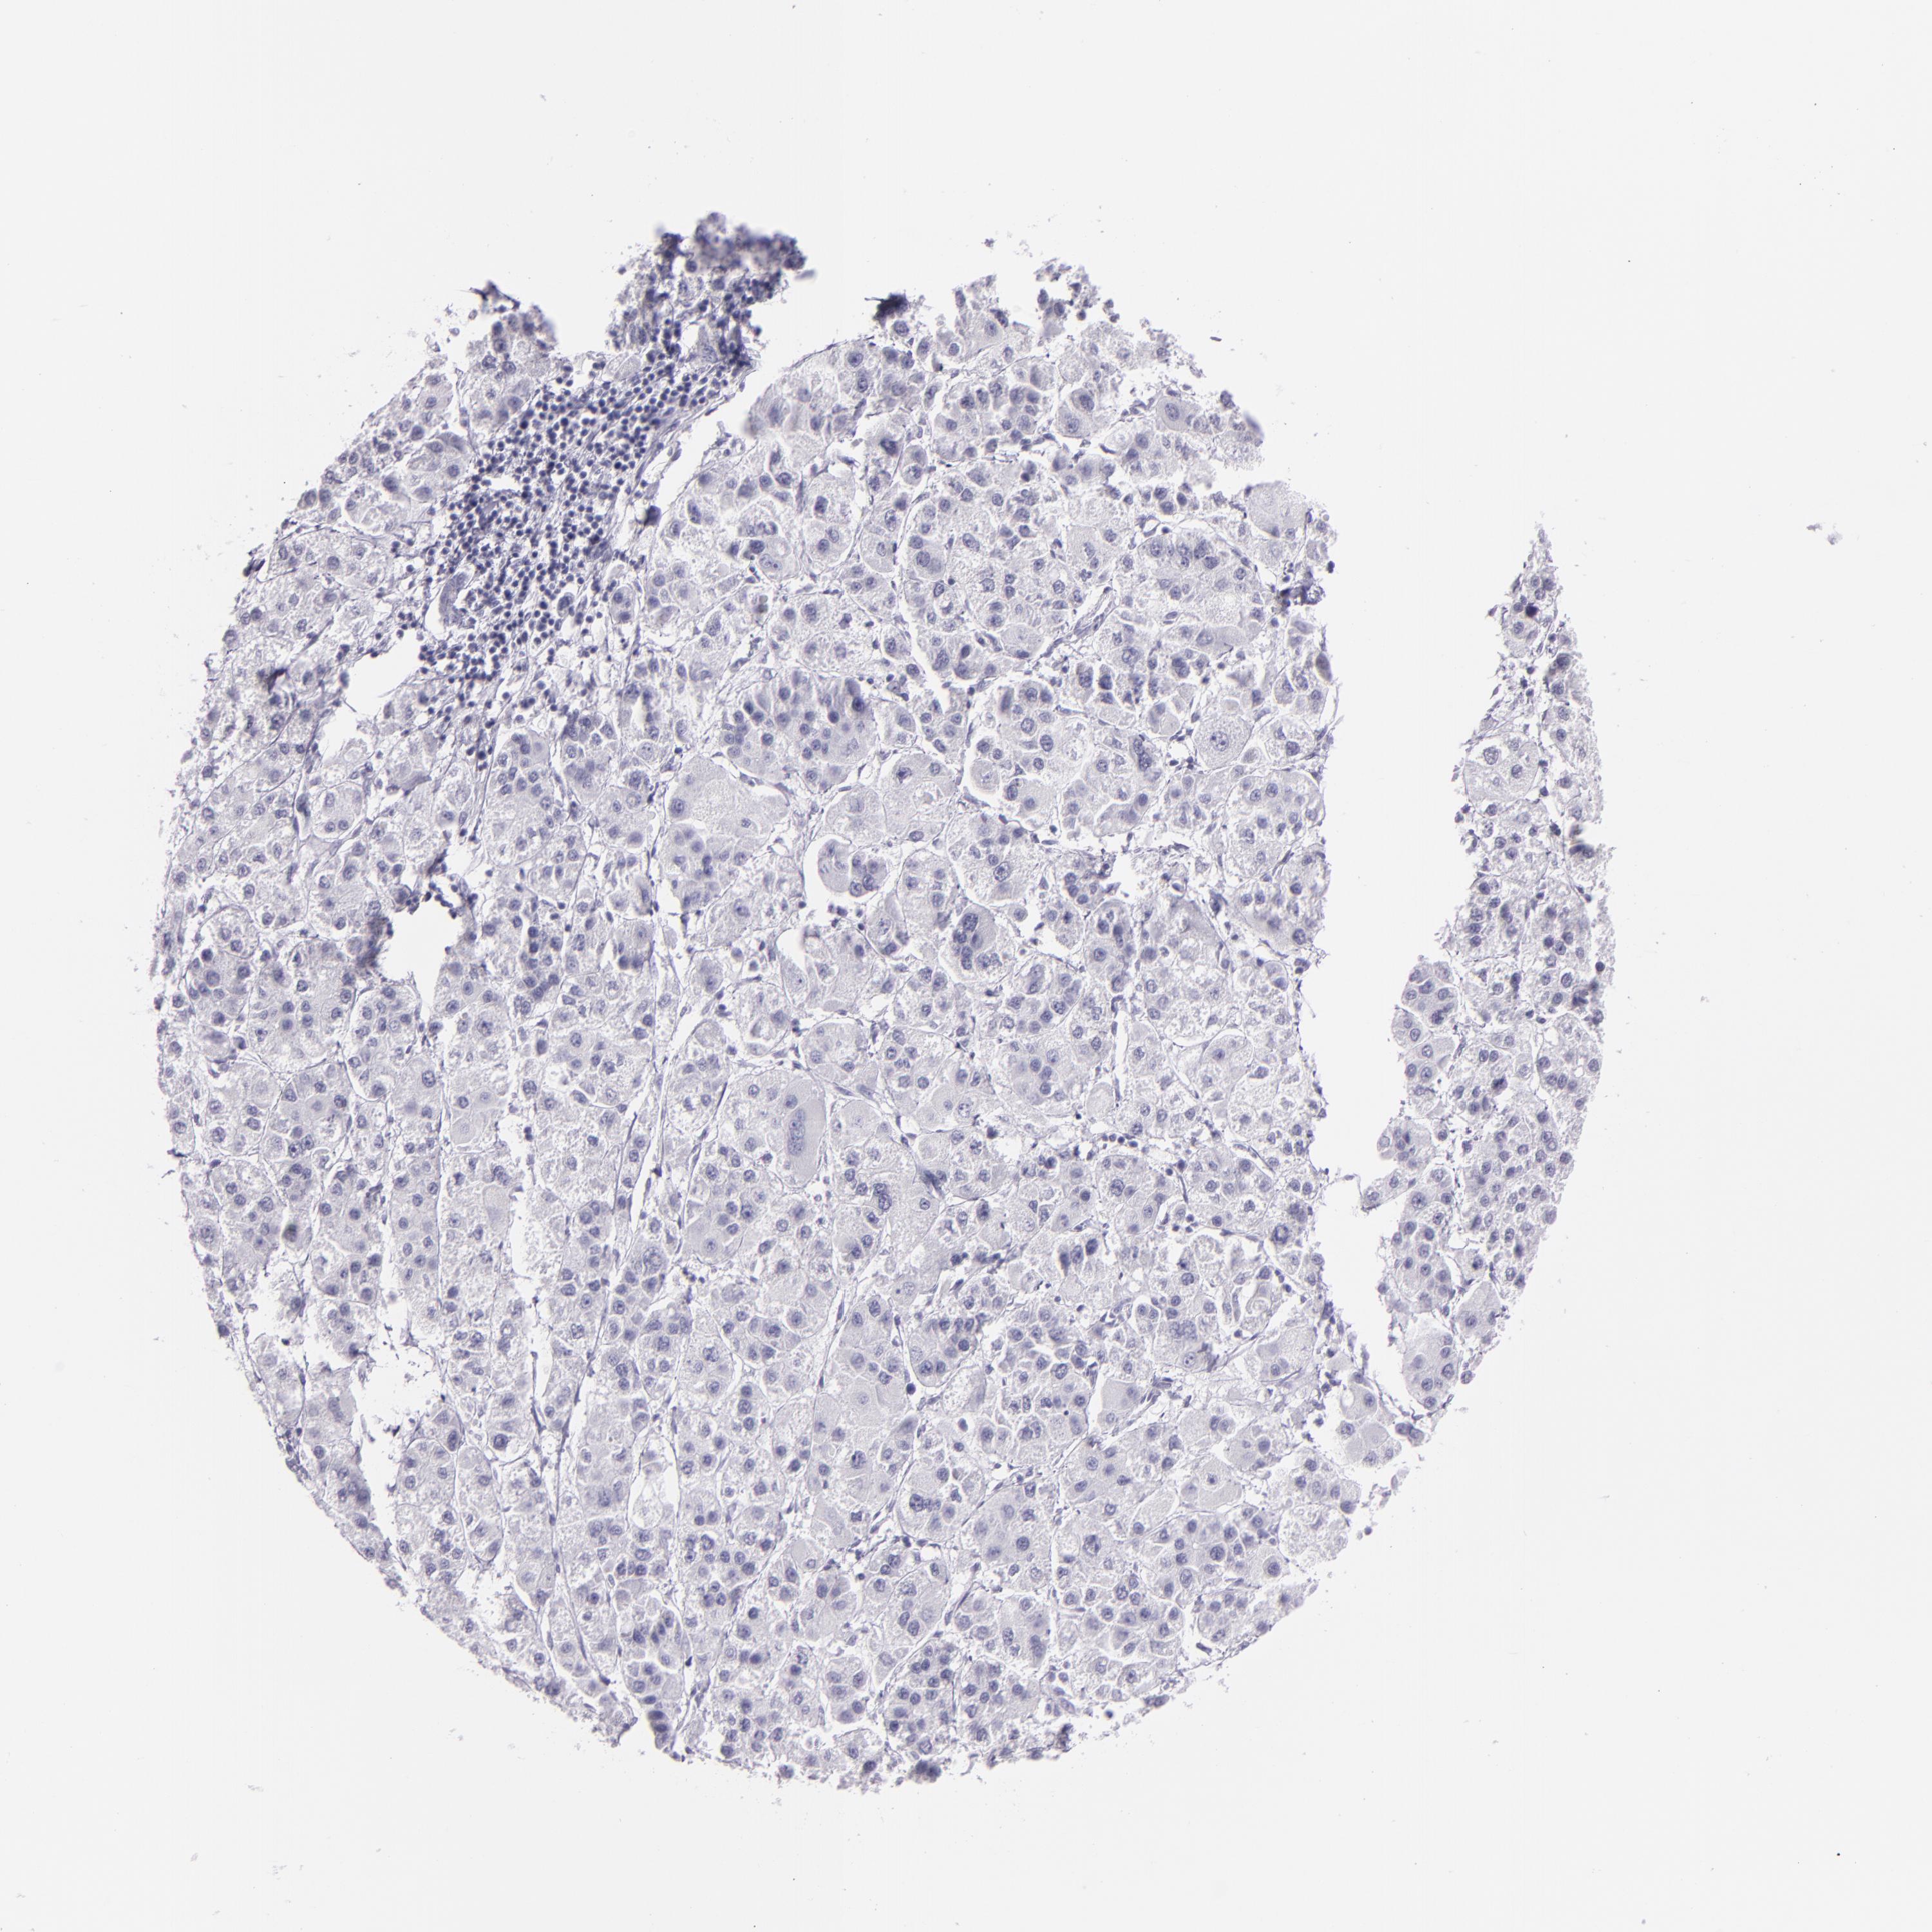

LIVER CANCER - Protein expressioni

A mouse-over function shows sample information and annotation data. Click on an image to view it in a full screen mode. Samples can be filtered based on level of antibody staining by selecting one or several of the following categories: high, medium, low and not detected. The assay and annotation is described here.

Note that samples used for immunohistochemistry by the Human Protein Atlas do not correspond to samples in the TCGA dataset.

Antibody stainingi

Antibody staining in the annotated cell types in the current human tissue is reported as not detected, low, medium, or high, based on conventional immunohistochemistry profiling in selected tissues. This score is based on the combination of the staining intensity and fraction of stained cells.

Each image is clickable and will lead to virtual microscopy that enables deeper exploration of all samples and also displays staining intensity scores, fraction scores and subcellular localization as well as patient and tissue information for each sample.

Antibody CAB002165

Staining

High

Medium

Low

Not detected

Intensity

Strong

Moderate

Weak

Negative

Quantity

>75%

75%-25%

<25%

None

Location

Nuclear

Cytoplasmic/membranous

Cytoplasmic/membranous,nuclear

Carcinoma, Hepatocellular, NOS

Cholangiocarcinoma